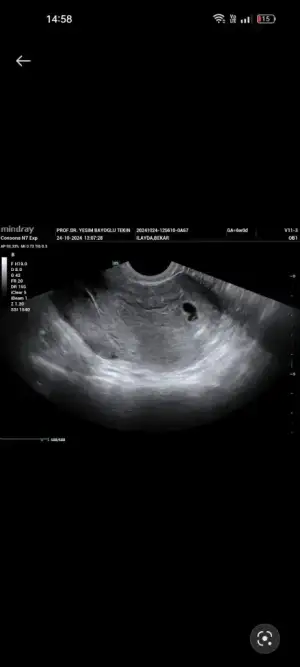

Merhaba bugün ikiz gebeliğe hamile olduğumu öğrendim fakat keselerden büyük olan boş diğerinde bebek gözüktü beta 10447 6 haftalık dedi bilgisi olan varsa yazabilirmj

Eklentiler

• Screenshot_2024-10-24-14-58-17-10_99c04817c0de5652397fc8b56c3b3817.webp

Screenshot_2024-10-24-14-58-17-10_99c04817c0de5652397fc8b56c3b3817.webp

11,4 KB · Görüntüleme: 75

• Screenshot_2024-10-24-14-58-07-70_99c04817c0de5652397fc8b56c3b3817.webp

Screenshot_2024-10-24-14-58-07-70_99c04817c0de5652397fc8b56c3b3817.webp

10,7 KB · Görüntüleme: 73